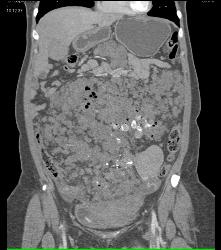

Hemangiomatosis in Klippel-Trenaunay-Weber (KTW) Syndrome